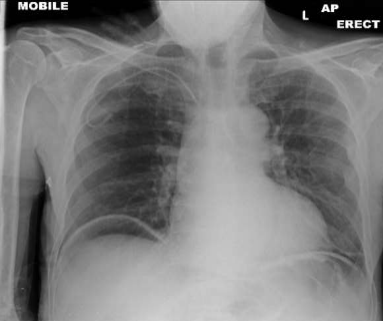

He underwent gastroscopy and colonoscopy which were normal. A CT chest, abdomen, and pelvis was then requested to exclude malignancy. However, it was reported as presence of a long segment of markedly dilated small bowel with air in the bowel wall, which appears to be the ileum. There were no peritoneal or pulmonary deposits and no definite obstructing lesion was visible. There was, however, a suspicious lesion in the ileo-cecal region. The reporting radiologist came to conclusion as distal small bowel obstruction with perforation. CXR and AXR were consistent with the findings of pneumatosis intestinalis.

Figure 1: CXR demonstrated air below diaphragm